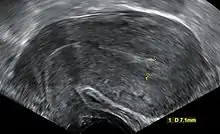

معايير الأشعة فوق البنفسجية: اثبتت الدراسات في المجلة الطبية في انجلترا معتمدة على منظمة الاشعة والاشعة فوق البنفسجية في أمريكا. حيث حددت المعايير التي يثبت فيها الإجهاض.[37]

- يجب أن يكون طول الجنين على الاقل 7 ملم وبدون نبض [الإنجليزية]

- يجب ان يكون قطر كيس الحمل من 16 – 24 ملم وبدون بويضة مخصبة

- غياب النبض بعد 7-13 يوم بعد اخذ الاشعة فوق البنفسجية التي اظهرت كيس الحمل بدون بويضة مخصبة

- غياب الجنين بعد 6 اسابيع من آخر دورة شهرية

- الكيس الامينوسي يظهر بشكل محاذ لكيس البويضة مع عدم وجود بويضة.

- كيس البويضة طوله أكثر من 7 ملم

- كيس الحمل حجمه أصغر من الجنين (يكون هناك فرق في الاطوال بين كيس الحمل وطول الجنين